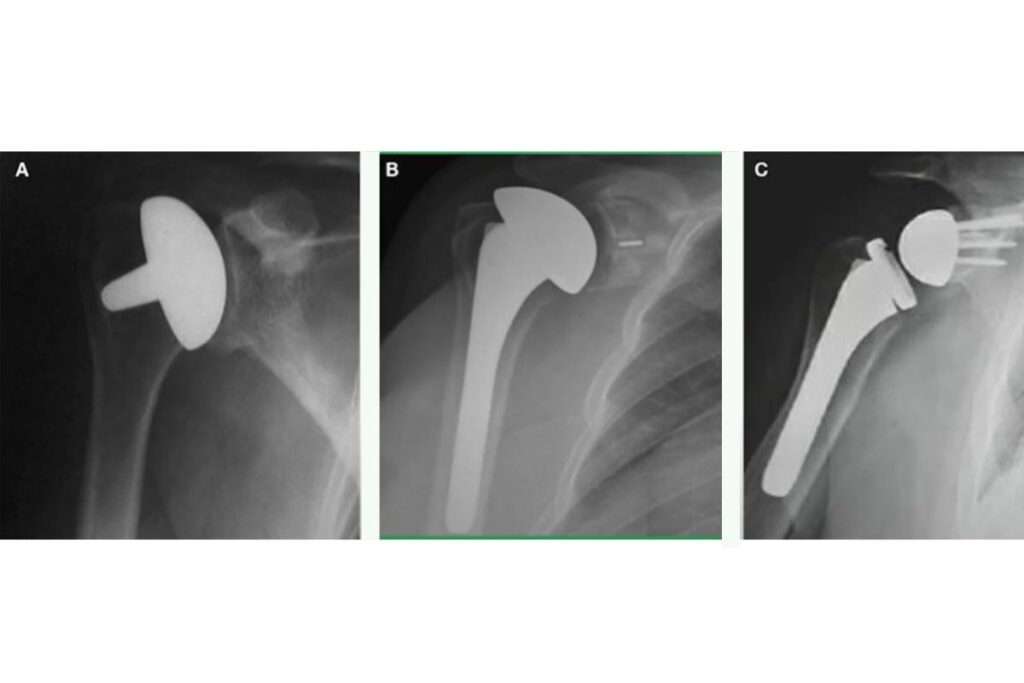

(A)Prótese parcial

Substitui apenas a cabeça do úmero, preservando a superfície articular da glenoide.

É indicada, principalmente, em casos de fraturas complexas do úmero ou quando a cartilagem da glenoide se mantém preservada.

(B)Prótese anatômica total

Reproduz a anatomia natural do ombro, substituindo tanto a cabeça umeral quanto a cavidade glenoidal. Para alcançar bons resultados, exige que o manguito rotador esteja íntegro, garantindo força e mobilidade adequadas.

(C) Artroplastia reversa

Inverte a anatomia da articulação, fixando a esfera na glenoide e a cavidade no úmero. É indicada em casos de lesão irreparável do manguito rotador ou em pacientes com artrose avançada, pois permite que o músculo deltóide assuma a função de movimentação do ombro.